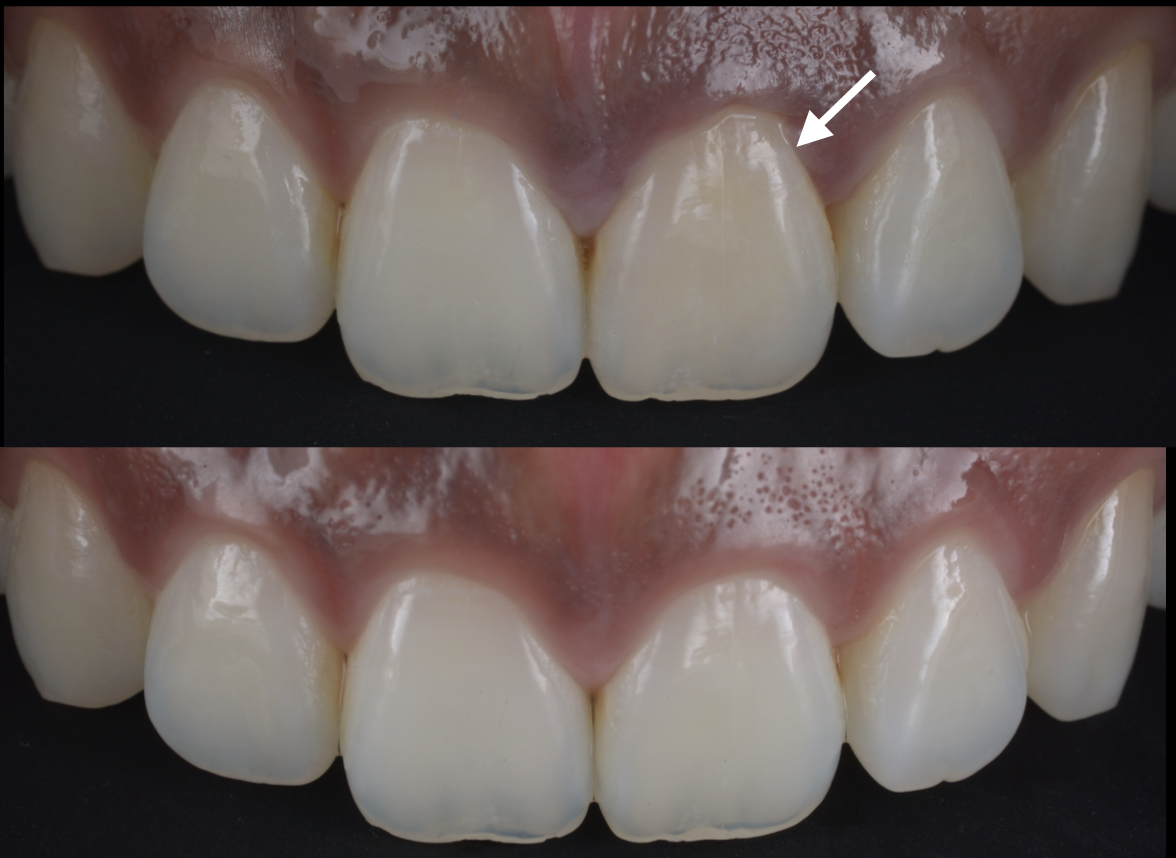

池袋で「すきっ歯(正中離開)」治療をテーマにセ...